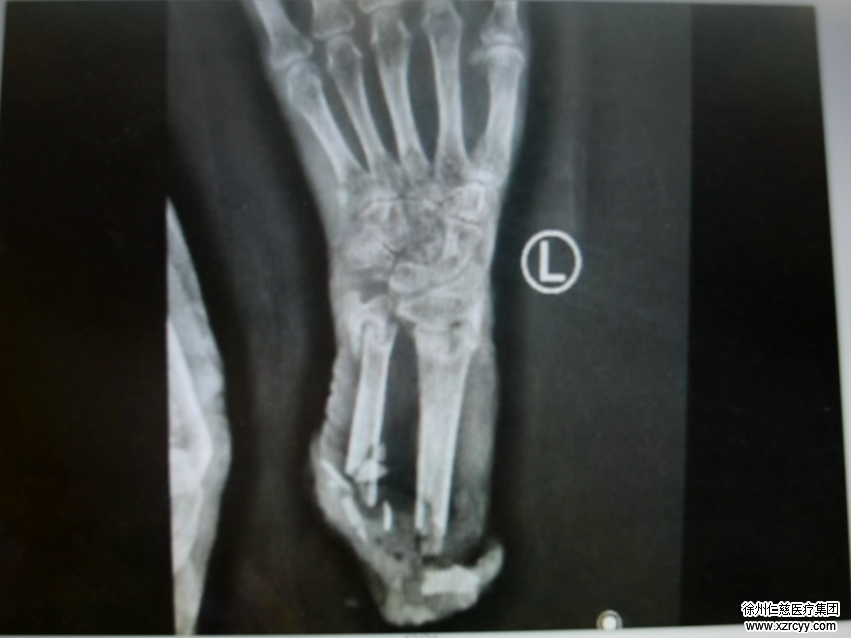

马师傅看见这情景吓坏了,他一边喊,一边赶紧跳下拖拉机用手里的木撬去挡风扇,可情况太危急,短短的几秒,左老太的左臂就已经被风扇绞得血肉模糊,整个人都差点被风扇绞进去。马师傅赶紧停掉风扇开关,用衣服简单地包扎了一下左老太的伤口,赶紧送往医院。因为老太年事已高,加上失血过多,当时已经处于休克状态,情况十分危急,经betway在线登陆急诊的医生接诊后,左老太被诊断为:左前臂离断、左大腿皮肤及软组织撕脱、额头出血,伤情十分严重。

紧接着,betway在线登陆脑外科的专家进行头部伤口的缝合,手外科的专家进行左臂伤口的清创处理。3小时的高度精神紧张,让滕道练浑身都湿透了。因为局部麻醉,老太太尚有意识,进行手术的同时,滕道练还得哄着老太太,和她说说话,让她精神放松。“老太太左臂伤口污染太重,全是泥土和麦穗,断肢也不例外,年纪太大,成活率太低了,这样肯定要截肢了。”滕道练表示,“如果伤口感染了,治疗起来可能更麻烦,截肢范围可能要扩大。”据悉,左老太的左腿皮肤大面积撕脱,骨外露,后期可能还要进行植皮手术。